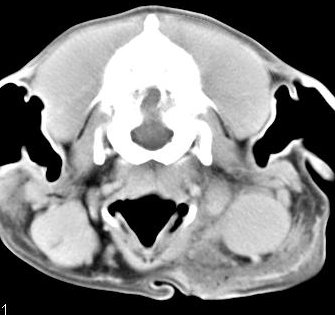

imágenes de TC en el perro | ||||||||||

ejemplo de imágenes de TC en el perro. Nótese la celulitis en la región parotídea izquierda | ||||||||||